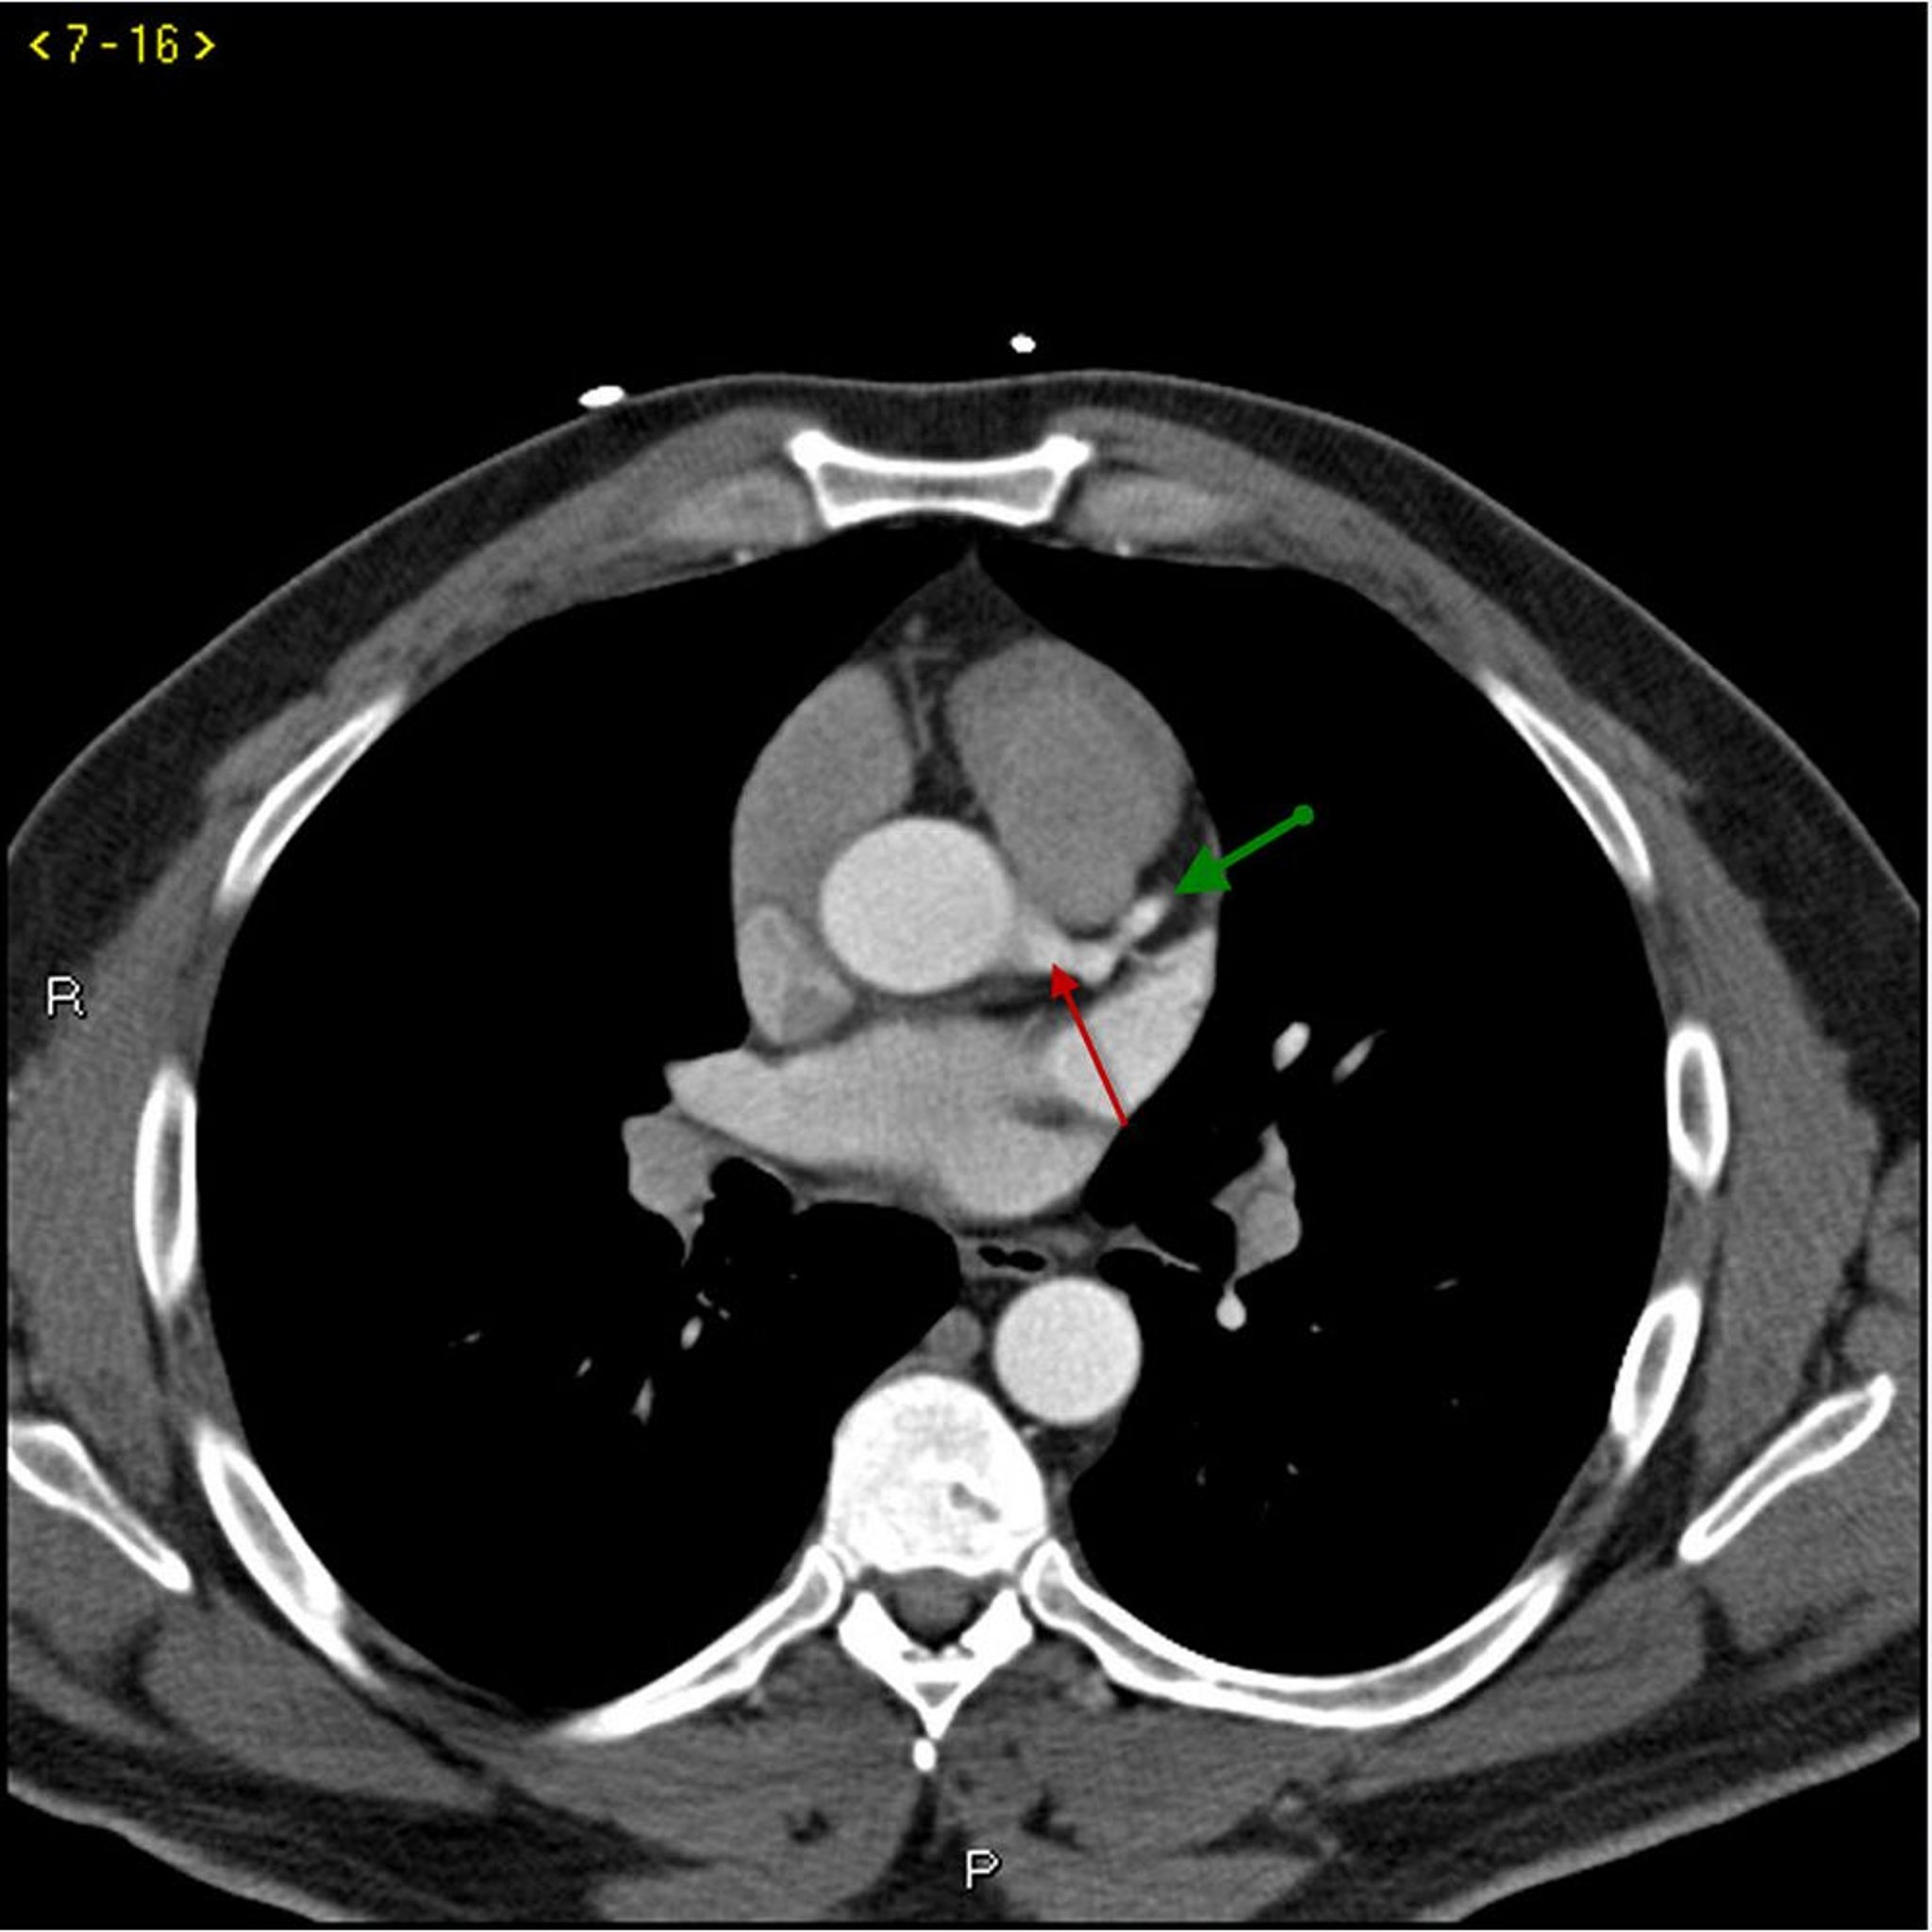

TDM avec contraste montrant des artères coronaires normales – Coupe 1

Cette TDM avec contraste montre des artères coronaires normales. Le tronc commun coronaire gauche est indiqué par la flèche rouge. Les artères interventriculaire antérieure gauche et circonflexe gauche sont indiquées par les flèches verte et bleue respectivement et l'artère coronaire droite est indiquée par la flèche violette.